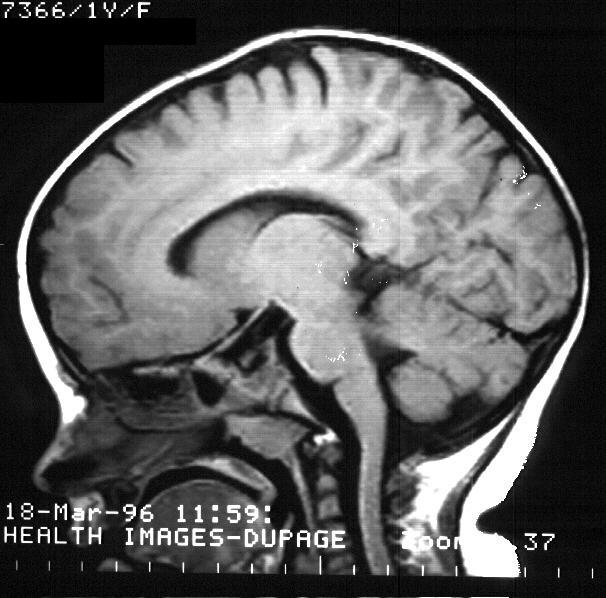

MRI of the brain and EEG had both been previously performed

and were normal. No additional studies were deemed necessary at the time

of the ER visit.